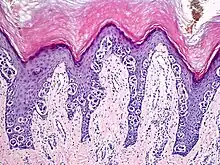

An acral nevus is a cutaneous condition of the palms, soles, fingers, or toes (peripheral body parts), characterized by a skin lesion that is usually macular or only slightly elevated, and may display a uniform brown or dark brown color, often with linear striations.[1]:1726

They are brown to dark brown in color and have linear streaks of darker pigmentation. Size is usually 7 mm or less, oval or spindle shaped, and well-demarcated. They become stable after an initial growth phase, and the number of lesions also decreases; a new lesion in middle-aged or elderly people should raise suspicion of acral lentiginous melanoma.